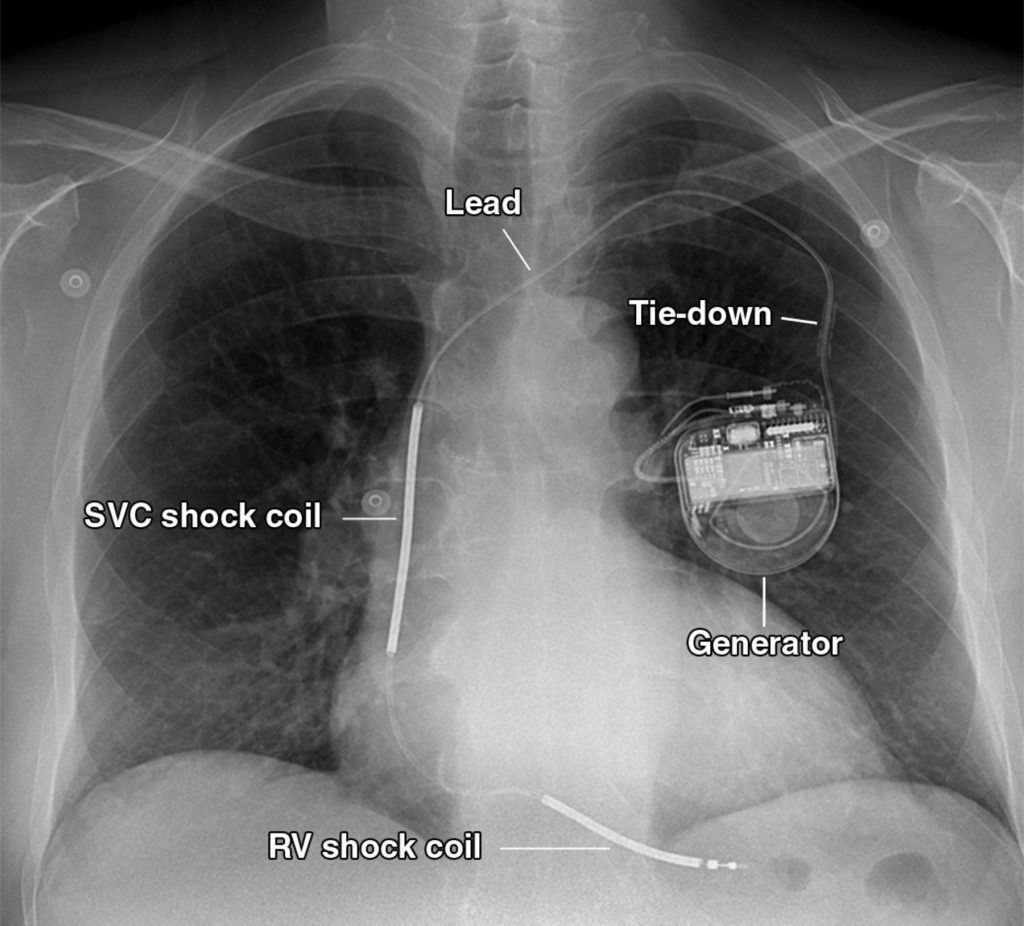

First Source Industries excels in the manufacturing of critical cardiac rhythm management devices, including pacemakers. Our expertise encompasses the entire product lifecycle, from design and development to production and assembly. With a deep understanding of the stringent regulatory requirements in this sector, we deliver high-precision components and assemblies that meet the highest quality standards. Our commitment to patient safety drives our meticulous manufacturing processes and ensures the reliability of every device we produce.